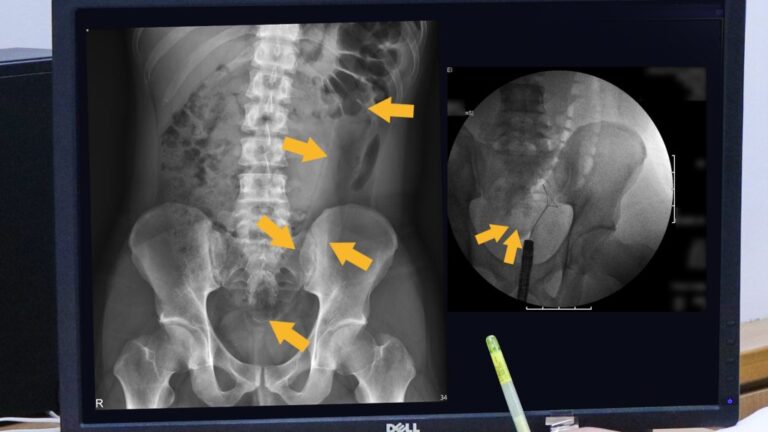

▲羅東博愛醫院醫療團隊特殊技術,成功取出…